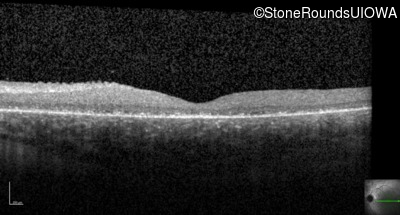

Optical Coherence Tomography - Left - 3/200 sc

Exemplar / OCT Stack